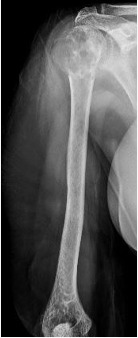

A suspeita de um tumor ósseo é feita através da avaliação minuciosa da queixa do paciente e exame físico. A partir da suspeita é realizada a triagem de exames que envolve Radiografias, Tomografia Computadorizada, Ressonância Magnética e Cintilografia Óssea, além de exames de sangue. Após o estudo dos exames, pode ser recomendada a biópsia do tecido do tumor. A biópsia é um procedimento que auxilia a especificar qual tumor e sua agressividade. Ela pode ser feita por meio de uma incisão ou por agulha.

Osteossarcoma: é o tumor ósseo maligno primário mais comum dentre crianças e adolescentes. Acomete principalmente os ossos dos joelhos, ombros e quadris.